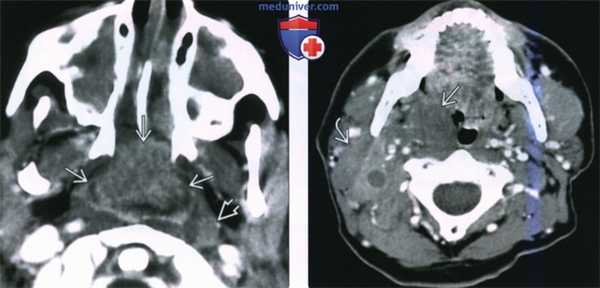

(Слева) При КТ с КУ в аксиальной проекции у ребенка со СПИД в области глоточной миндалины определяется крупная неходжкинская лимфома, неоднородно накапливающая контраст. Обратите внимание на увеличенный лимфоузел в заглоточном пространстве слева и на практически полную обструкцию просвета носоглотки. Полость носа и верхнечелюстные пазухи с обеих сторон заполнены доброкачественным секретом.

(Справа) При КТ с КУ в аксиальной проекции визуализируется мультифокальная неходжкинская лимфома с вовлечением правой небной миндалины, а также группа спаянных лимфоузлов II уровня. Шейная аденопатия встречается в 50% случаев неходжкинских лимфом слизистого окологлоточного пространства.